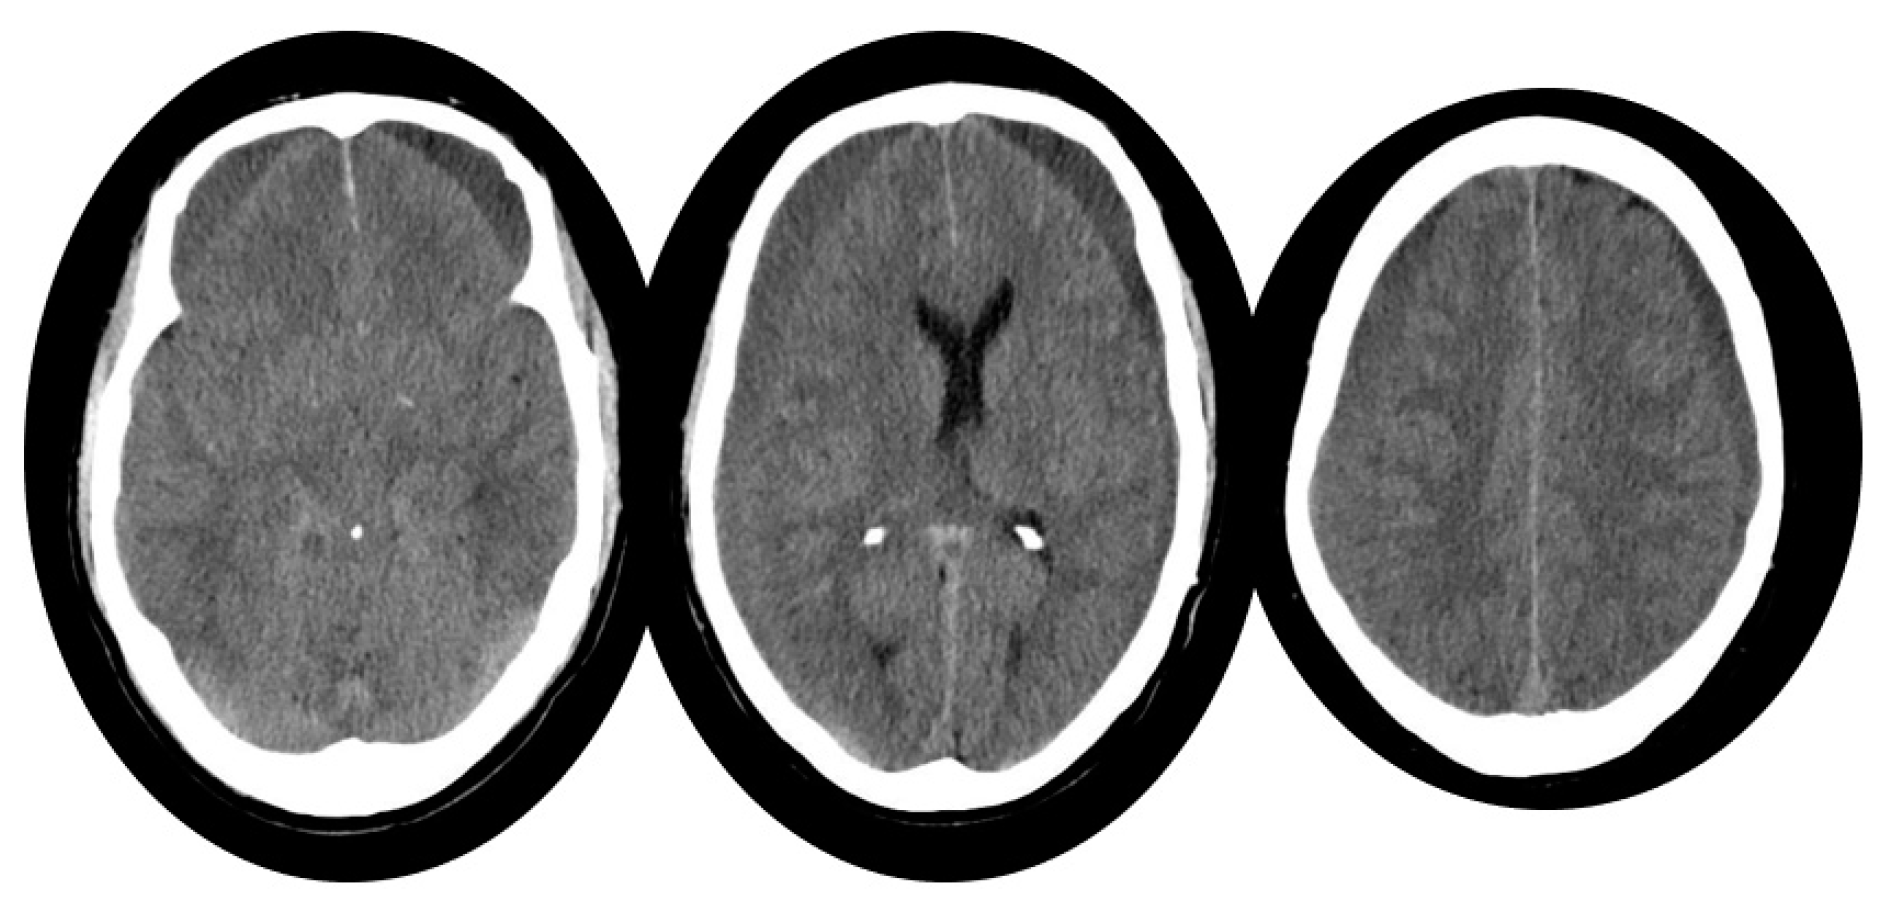

2. Case Report